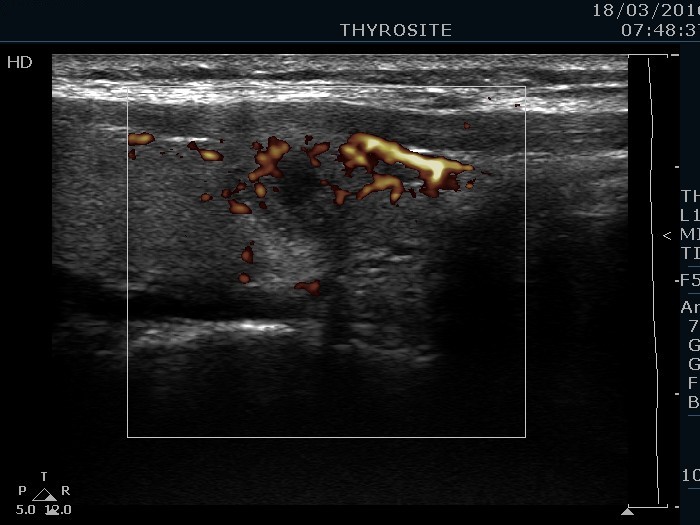

The borders of the nodule - case conp 055 (ultrasonographic picture 7)

Right lobe, longitudinal scan, color Doppler mode.